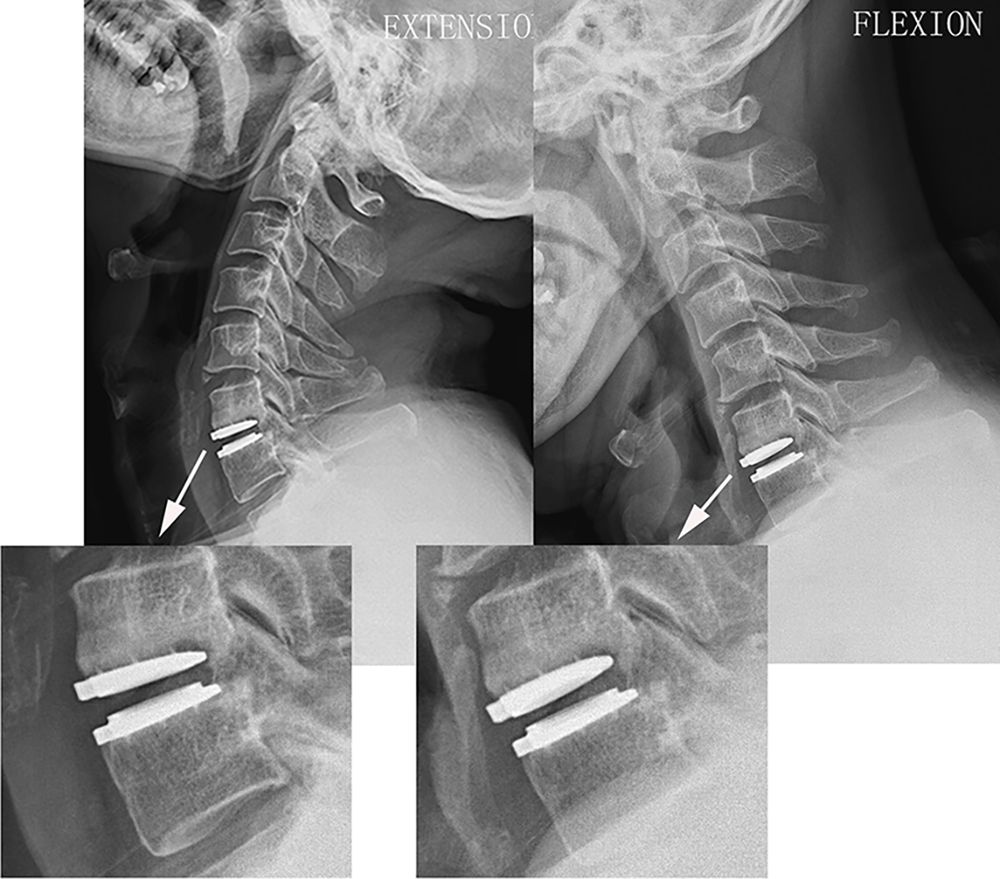

Для динамічної стабілізації шийного відділу хребта (DCI) використовуються спеціальні системи, які передбачають встановлення спеціального імпланту між тілами шийних хребців переднім доступом замість видаленого міжхребцевого диска.

Відмінною особливістю динамічних систем стабілізації хребта є те, що вони дозволяють усунути розвиток нестабільності в ураженому сегменті і запобігти розвитку дегенеративних змін в суміжних хребетно-рухових сегментах. Збереження рухливості в оперованих і суміжних з ними сегментах забезпечує фізіологічну повноцінність функцій хребта.